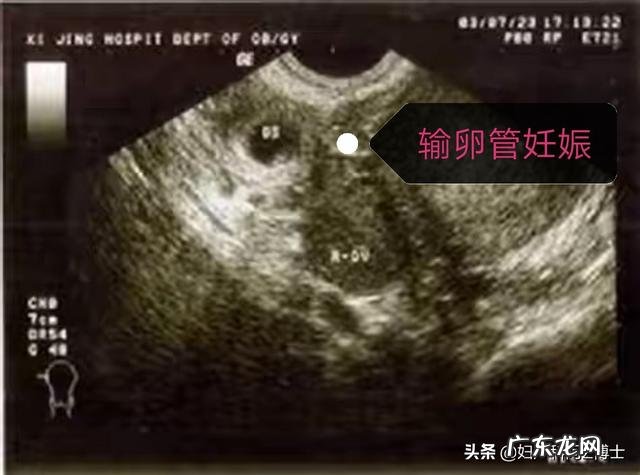

宫外孕就像怀孕女性的一根心头刺 , 扎在每一个孕妇心里 , 每个孕妇都害怕 , 自己如果是宫外孕了该怎么办呢?一.宫外孕的是与非:宫外孕的医学名词叫做异位妊娠 , 即非子宫内膜以外的着床并且发育的妊娠类型 。这里面就涉及到宫外孕想要被发现 , 就必须受精卵想到一定程度大小才可以被彩超准确捕捉到 。如果超过孕5周以上 , 彩超基本都能发现孕囊是在宫腔内还是在宫腔外 , 如果低于5周以下 , 宫内宫外有时候也难以分清 。

二.宫外孕的鉴别:判定的标准有两个 , 一个是血HCG(人促绒毛膜促性腺激素)的波动水平 , 另外一个是妇科彩超的检查结果;如果是HCG一般值超过2000 , 在子宫或是子宫周围都能通过彩超看到孕囊;如果值低于2000以下 , 需要看HCG的翻倍情况 , 如果隔一天检查HCG翻倍小于正常的65% , 那么提示宫外孕的存在 , 需要警惕 。

三.不流血是不是就不是宫外孕了?这个观点是错误的 , 宫外孕也有不阴道流血的情况 , 比如输卵管妊娠的流产型 , 可能就没有阴道流血 , 但是输卵管就已经显示妊娠迹象了 。如果一个女性停经了 , 检查出来是怀孕了 , 有阴道流血 , 此时可能为先兆流产、难免流产,也可能为宫外孕;如果没有阴道流血 , 怀孕5周没有在宫腔内见到孕囊 , 也应该重视宫外孕的发生 , 需要在第六周做彩超 , 以及隔天测孕早两项 。